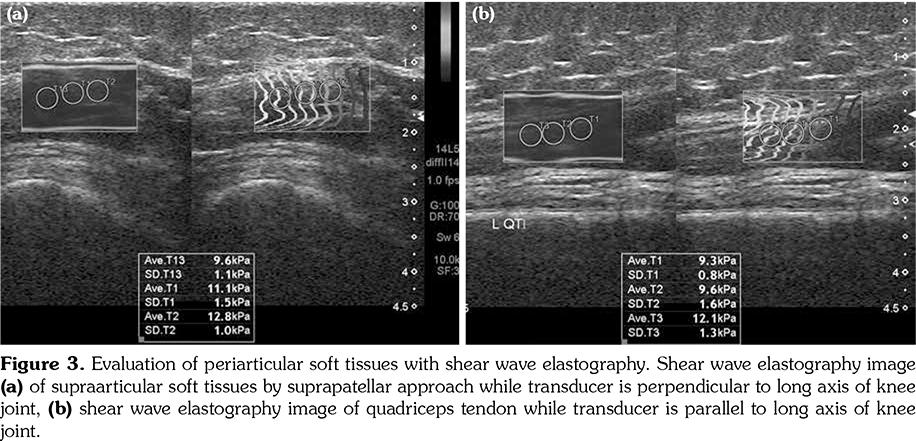

All patients and healthy volunteers were screened with Canon Aplio 500 Platinum US device (Canon Medical Systems, Tokyo, Japan) equipped with SMI, PD and SWE functions. All participants were examined in supine position and their knees were in extension (Figures 1, 2). Once the gray scale US examination confirmed the arthritis based on synovial thickening, joint effusion and periarticular echogenicity, then SMI and SWE were performed to the supraarticular and infraarticular soft tissues concerning the synovium and periarticular soft tissues. VI is a novel parameter determined for SMI and PD corresponding the ratio of colored pixels to the total pixels within the selected region of interest (ROI). VI was calculated automatically on colored SMI and PD images over the selected rectangular shaped ROI with edges measured 5x15 mm (Figure 3). Mean VI values were calculated by averaging results of three different acquisitions of PD and SMI. The ROI was placed perpendicular to the long axis of the knee joint at the supraarticular and infraarticular locations including the synovium and periarticular soft tissues. On SWE evaluation, the QT and PT were demonstrated along with their long axis. Three different ROIs for SWE were performed from the tendon halves closer to the knee joints. Each ROI was in circle shape and 3 mm in diameter. We depicted mean elasticity for PT, QT, supraarticular soft tissues (SAST) and infraarticular soft tissues (IAST) (Figures 4, 5).